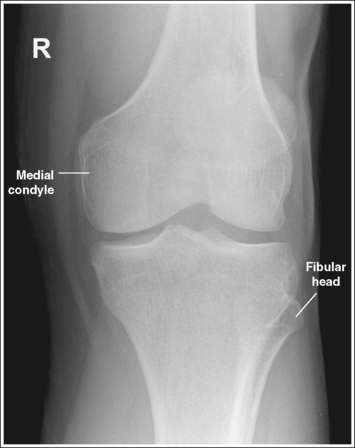

The knee demonstrates an AP projection. The medial and lateral femoral epicondyles are in profile, the femoral condyles are symmetrical, the intercondylar eminence is centered within the intercondylar fossa, and the tibia is superimposed over 0.25 inch (0.6 cm) of the fibular head.

• To obtain an AP knee projection, place the patient in a supine position with the knee fully extended. Internally rotate the leg until an imaginary line drawn between the medial and lateral femoral epicondyles is positioned parallel with the IR (Figure 6-71). This positioning places the medial and lateral femoral epicondyles at equal distances from the IR as well as medially and laterally in profile, respectively. It also centers the intercondylar eminence within the intercondylar fossa and draws the fibular neck and a portion of the fibular head from beneath the tibia.

• Effect of rotation. If the femoral epicondyles are not positioned parallel with the IR, an AP projection has not been obtained. If the patient's leg was not internally rotated enough to place the epicondyles at equal distances from the IR, they are not in profile, the medial femoral condyle appears larger than the lateral condyle, and the tibia is superimposed over more than 0.25 inch (0.6 cm) of the fibular head (see Image 54). If the patient's leg was internally rotated more than needed to place the femoral epicondyles at equal distances from the IR, the epicondyles are not demonstrated in profile, the lateral femoral condyle appears larger than the medial condyle, and the tibia is superimposed over less than 0.25 inch (0.6 cm) of the fibular head (see Image 55).

The knee joint space is open, the anterior and posterior condylar margins of the tibia are superimposed, the intercondylar eminence and tubercles are demonstrated in profile, and the fibular head is demonstrated approximately 0.5 inch (1.25 cm) distal to the tibial plateau.

• The anterior and posterior condylar margins of the tibia are superimposed if the correct central ray angulation, as determined by the patient's upper thigh and buttocks thickness, is used. By studying the tibial plateau region, you will see that the tibial plateau slopes distally approximately 5 degrees from the anterior condylar margin to the posterior condylar margin on both the medial and lateral aspects (Figure 6-72). Only if the central ray is aligned parallel with the tibial plateau slope is an open knee joint space obtained.

• Center the central ray to the midline of the knee at a level 1 inch (2.5 cm) distal to the palpable medial epicondyle to place the knee joint in the center of the exposure field. (As long as the knee remains extended, an alternative central ray placement is 0.5 inch (1.25 cm) distal to the patellar apex.) Open the longitudinal collimation enough to include one fourth of the distal femur and proximal lower leg. Transverse collimation should be to within 0.5 inch (1.25 cm) of the knee skin line.

The femoral epicondyles are not in profile, the medial femoral condyle appears larger than the lateral condyle, and the fibular head demonstrates more than 0.25 inch (0.6 cm) of tibial superimposition. The leg was externally rotated.

Internally rotate the leg until the femoral epicondyles are at equal distances from the IR.

The femoral epicondyles are not in profile, the lateral femoral condyle appears larger than the medial condyle, and the fibular head demonstrates less than 0.25 inch (0.6 cm) of tibial superimposition. The leg was internally rotated.

Externally rotate the leg until the femoral epicondyles are at equal distances from the film.